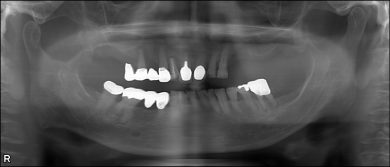

72歳女性 主訴 前歯が動いて咬めない。

パノラマレントゲンから、上の歯は前歯6本、右上小臼歯1本残存してますが、動揺度は2~3度。ほぼ3度。左上の部分床義歯は不安定でした。

18年前ですので、サージカルガイドの精度はイマイチで、右上の臼歯部は造骨処置(いわゆるサイナスリフト)を行いました。